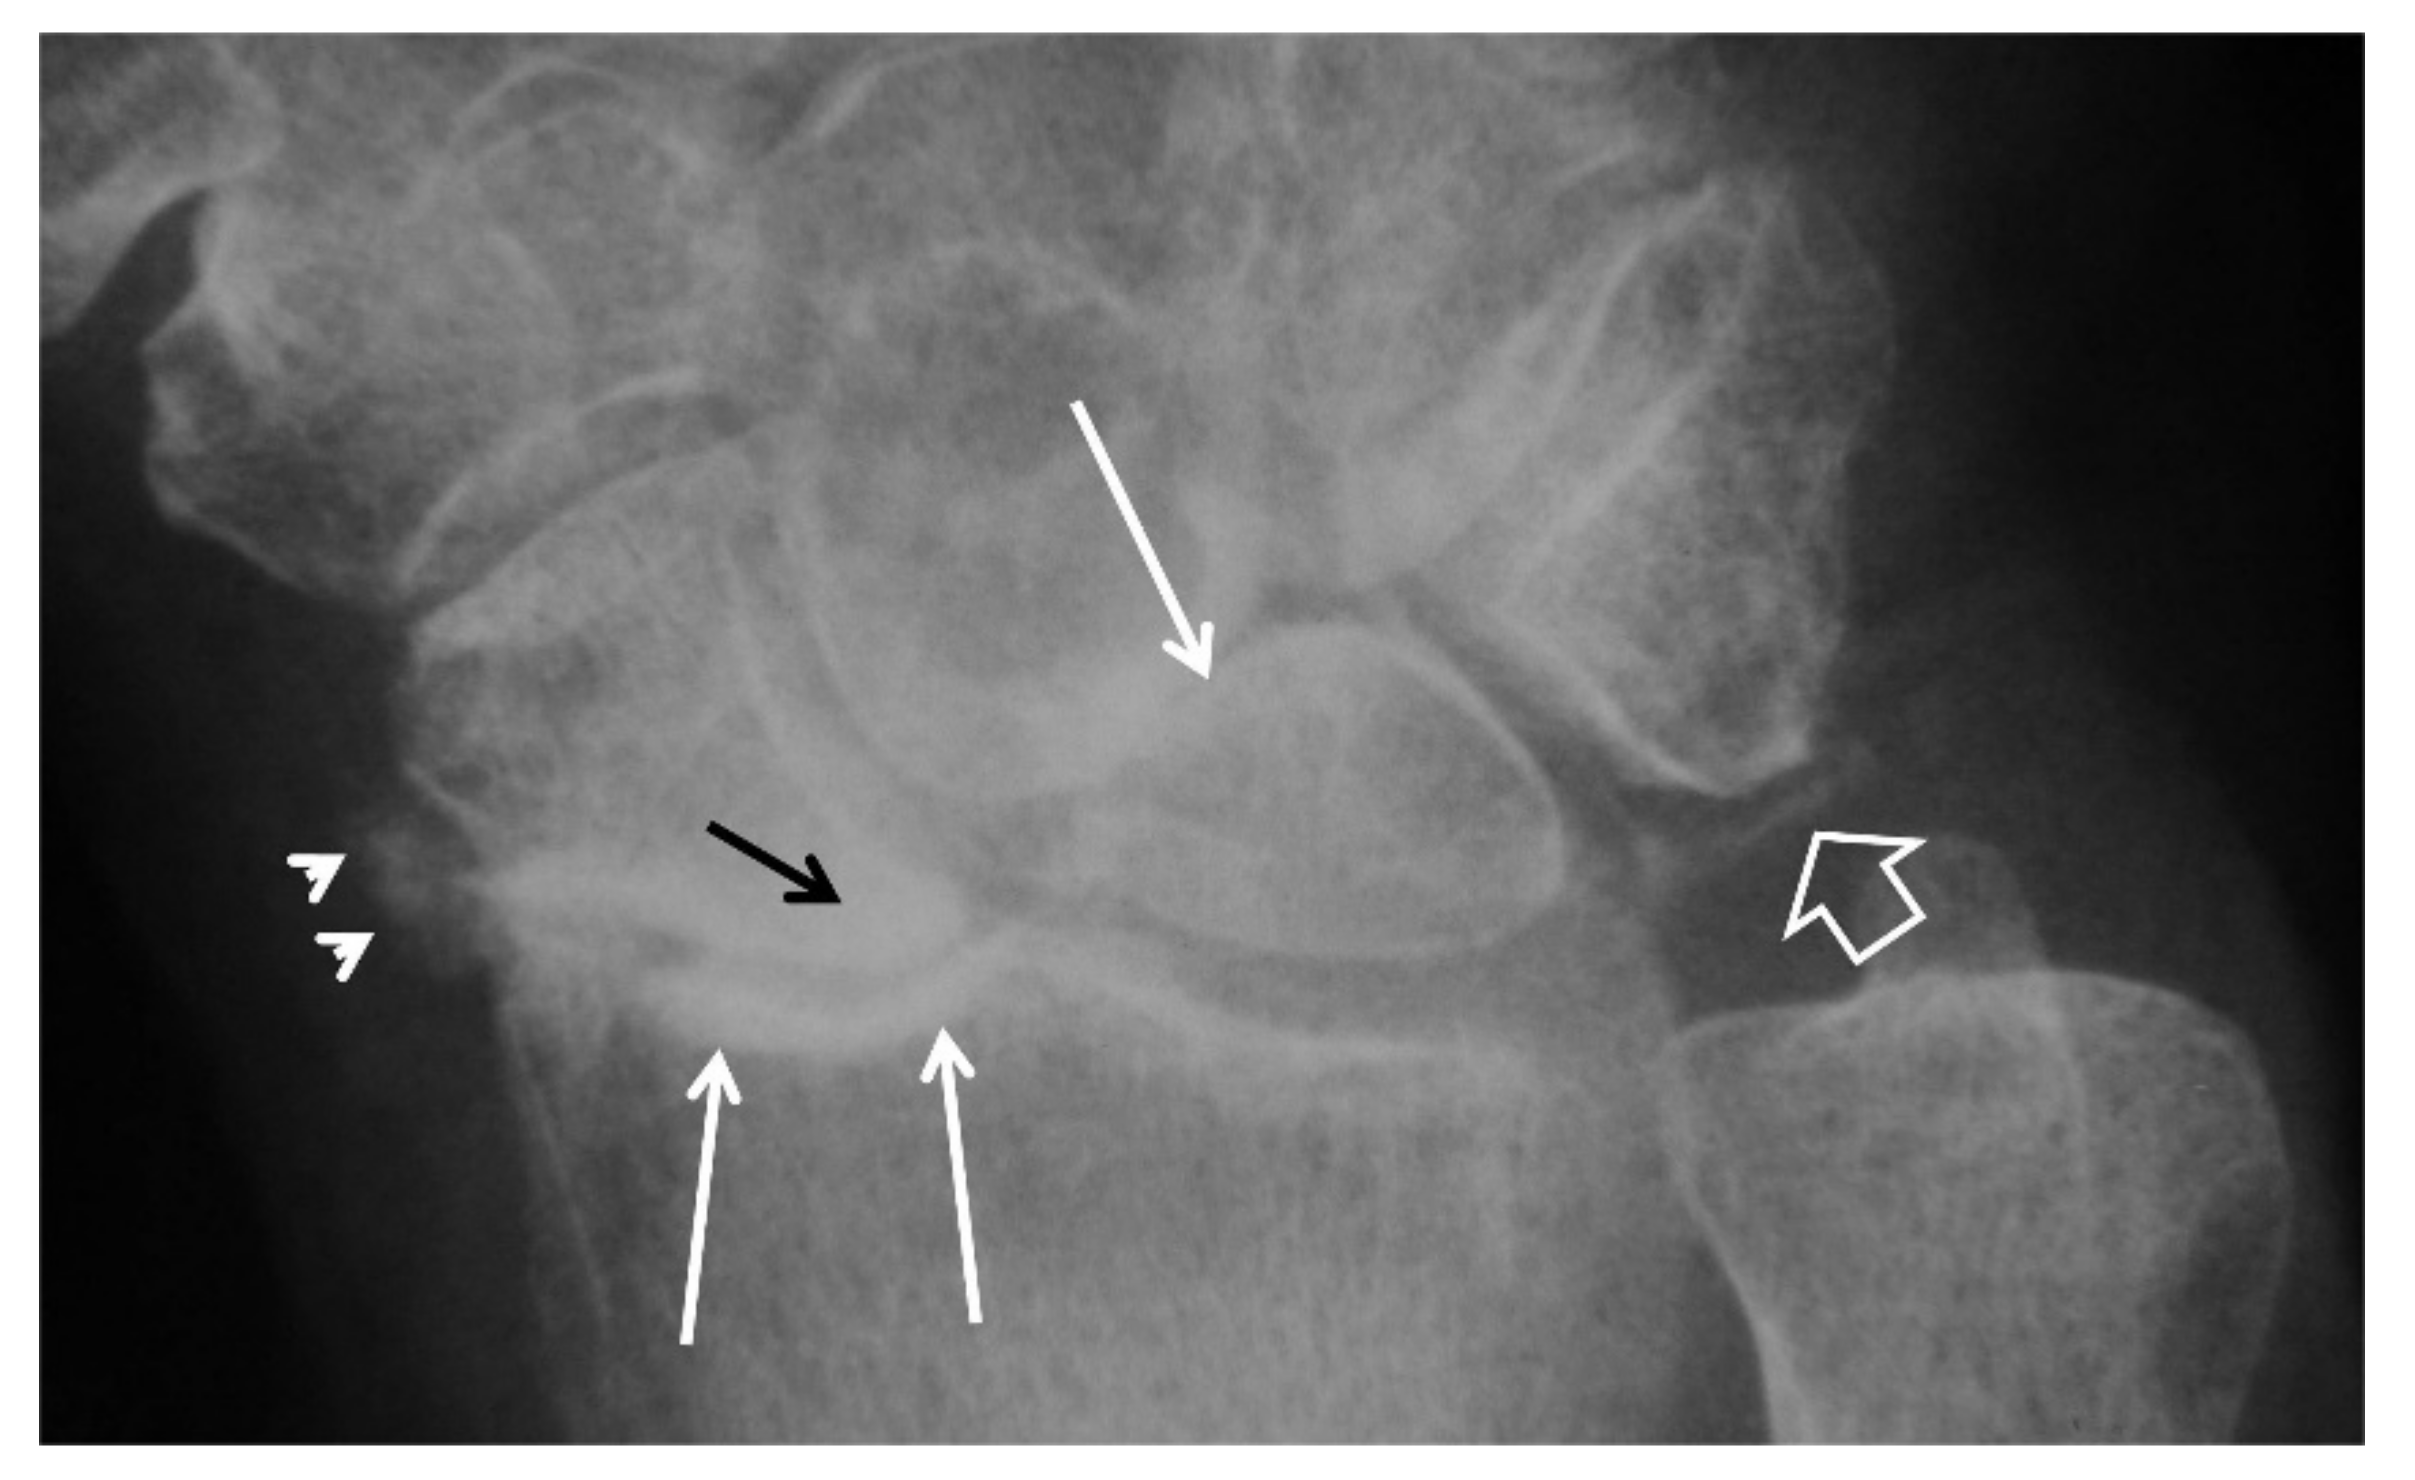

Figure 3.

PA radiographs. (A) A 35-year-old male patient with a history of wrist pain for 10 years. Scaphoid fracture non-union (arrow), proximal pole cyst formation (open arrow) and radial side joint space narrowing (short arrows) are diagnostic of stage I SNAC wrist. (B) A 44-year-old male patient known scaphoid osteonecrosis. Proximal pole osteonecrosis (black arrow) combined with radioscaphoid space narrowing (open arrow) and osteophytosis of the scaphoid bone (short white arrow) are diagnostic of a SNAC wrist. The proximal carpal arc is disrupted and the capitate bone is proximally migrated.